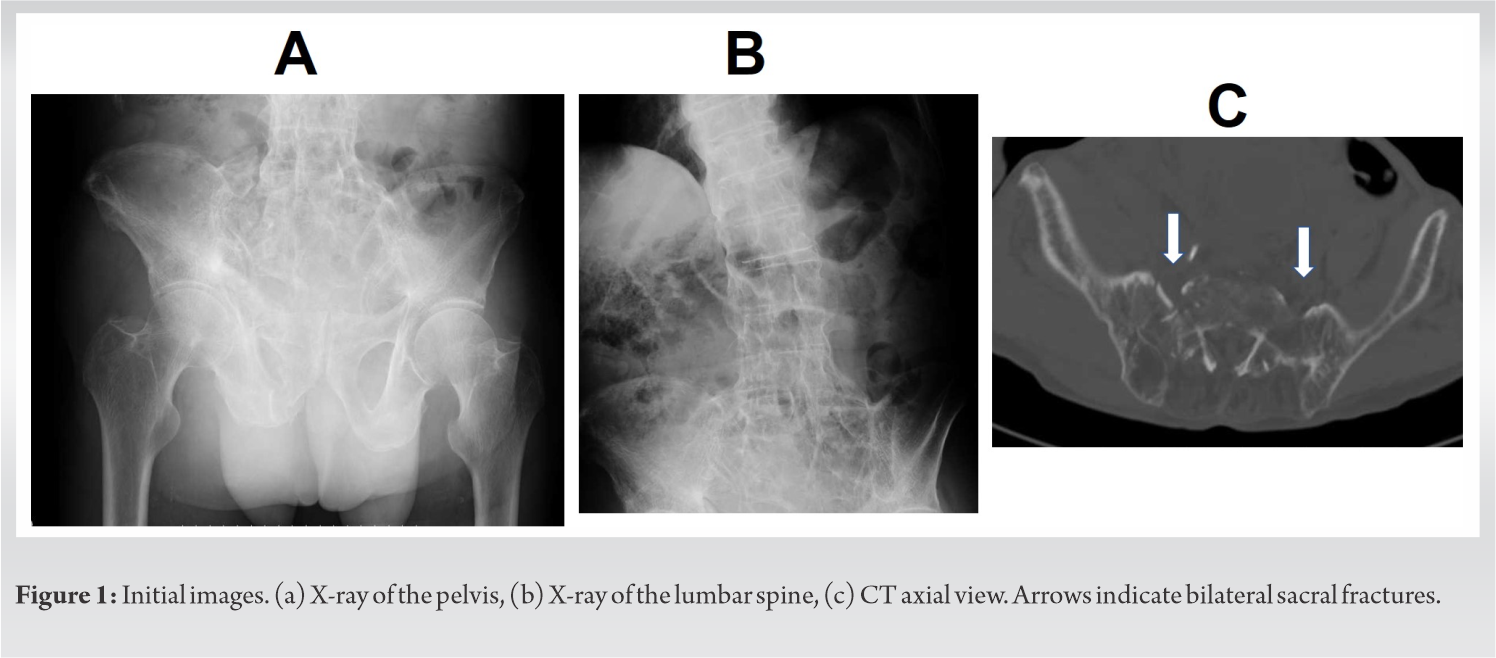

The estimated surgical time from posterior and anterior surgeries was 147 min and 49 min, respectively. Blood loss from posterior and anterior surgeries was 268 g and 150 g, respectively. The postoperative clinical course of the patient was uneventful and bony fusion was achieved as seen on X-ray obtained 1 year postoperatively even without any medical treatment for osteoporosis (Fig. 4).